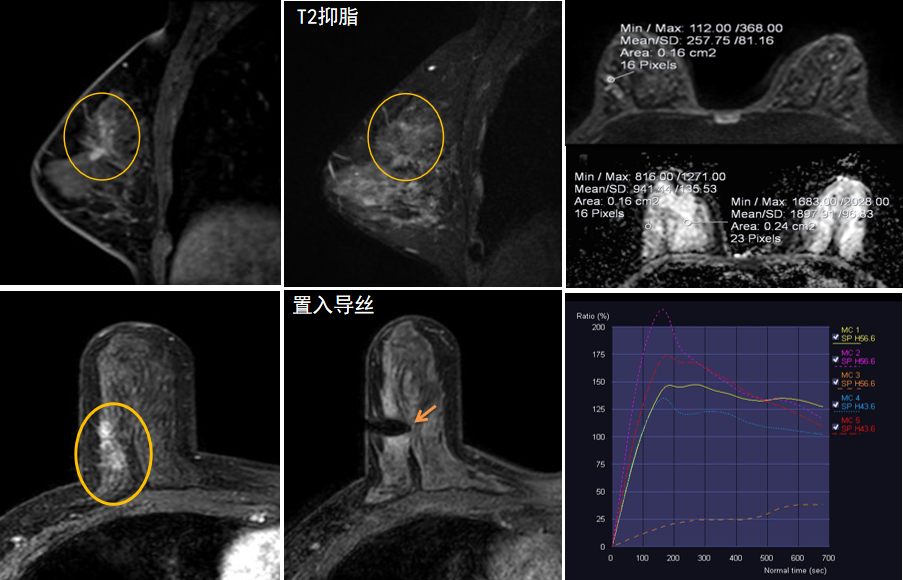

今年45歲的某女士,兩個月前行超聲檢查發(fā)現(xiàn)右乳結(jié)節(jié),乳腺X線攝影檢查提示右乳外上象限局部腺體結(jié)構(gòu)扭曲并簇狀無定形鈣化,為了進一步評估病變性質(zhì)并確定范圍進行了乳腺MR平掃 DWI 增強的檢查,經(jīng)MR評估發(fā)現(xiàn)右乳病變范圍較廣,評估為BI-RADS 4類可疑病變,需要取得病理學結(jié)果。

只能借助影像學引導,但超聲僅顯示了病變中的小結(jié)節(jié),X線攝影(鉬靶)顯示的病變邊界比較模糊,要想做到精準完整切除必須借助MR的引導,而這一技術(shù)對軟硬件平臺及人員技術(shù)都有很高的要求,因此,多年來一直是我國乳腺病變診療的盲區(qū),經(jīng)常是MR發(fā)現(xiàn)可疑病變但卻無法處理。目前全國僅有少數(shù)幾家醫(yī)院開展了這方面的部分工作。

陳寶瑩主任及其帶領的MR介入診療小組詳細詢問了病情,分析了患者資料,并與患者和臨床醫(yī)生進行了充分溝通,確定于手術(shù)前為患者實施MR引導下的病變穿刺導絲定位和體表范圍確定。手術(shù)前陳寶瑩主任帶領聶品醫(yī)師、馬小偉技師、韓愛萍護士長等MR介入診療小組成員,借助MR高清的圖像顯示和定位系統(tǒng),確定病變范圍,精準穿刺置入定位導絲,并準確標記出病變體表范圍,整個過程患者無任何不適。在定位導絲和體表范圍標記的輔助下,甲乳外科劉曉敏主任精準切除了病變,解除了患者的后顧之憂。

國內(nèi)外指南均建議40歲以上的女性每年行一次雙乳X線攝影(鉬靶)檢查,以篩查乳腺癌。對于乳腺癌高危人群40歲以前即建議開始乳腺癌篩查,除了進行乳腺X線攝影(鉬靶)篩查外需要補充MR檢查,MR檢查敏感性最高,能夠發(fā)現(xiàn)大量X線攝影和超聲檢查陰性的可疑病變,基于多模態(tài)、多參數(shù)的結(jié)構(gòu)和功能成像的基礎上,MR能夠精準顯示病變位置、范圍以及病變內(nèi)的活性區(qū)域,MR引導下的介入診療不但解決了僅在MR顯示的病變的處置難題,而且能夠精準定位活性區(qū)域,保證了定位、活檢及旋切的準確性。